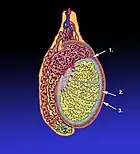

(Cilvēka) sēklinieks (2)

- (anatomy) testicle